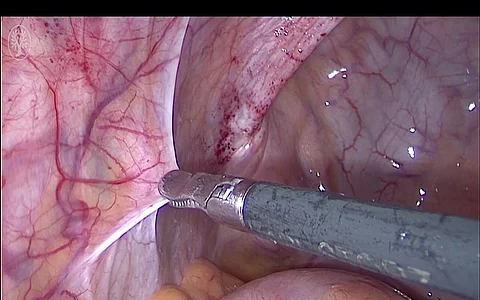

Laparoskopische Myomenukleation

Für Sie operierte Dr. Felix Neis aus dem Department für Frauengesundheit Tübingen. Moderiert wurde die OP von Dr. Felix Neis.